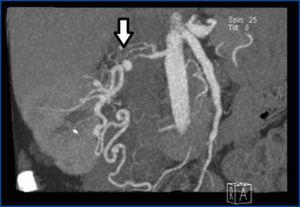

Tras la intervención, las cifras tensionales se normalizaron y desde entonces se mantiene alrededor de 120/80 mmHg sin fármacos. En el estudio de imagen poscirugía (angiorresonancia renal) (figura 2), se objetiva el injerto renal normal con nueva vascularización.

Figura 2. Angiorresonancia renal